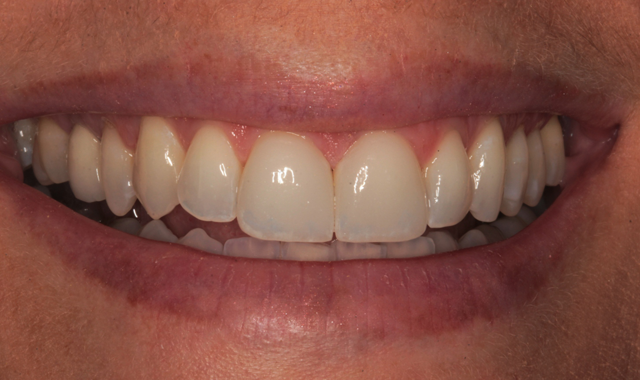

A young woman presented to my office for a consultation regarding her maxillary central incisors. She had porcelain veneers in place but was not satisfied with the color. Though she agreed that they looked good, she did not feel that they matched her adjacent teeth.

Figure 1 is a facial view of the first veneers in place. In the incisal view (Fig. 2), you can see that the veneers were used to close a central diastema. The reading from Vita Shade Light showed that the lateral incisors were 1M1 on the Vita 3D Shade Guide (Fig. 3).

Fig. 1 Fig. 2